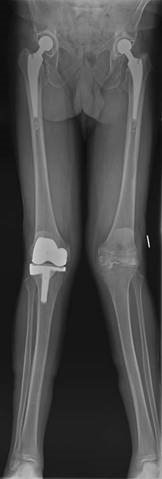

๐ŸŽ“ Viva 65

This is a picture of a 67-year-old woman with a painful left knee. The pain has been increasing over the last 3 years. She is otherwise fit and well and has had previous joint replacements as shown.

Illustration 11 for Ace FRCS Orthopaedics: Oxford University Press Adult Pathology Viva

๐Ÿ” Click to enlarge

Clinical Radiograph / Orthopedic Image

How would you manage this patient?

How would you consent the patient for a TKR?

Describe your plan for surgery in this case.

I would establish from the history more about her pain, disability, and what treatment she has so far received. On examination I would look at the nature of the deformity, whether it is correctable, the integrity of the medial collateral ligament, patella tracking, and neurological status (common peroneal nerve). I would examine her hip and foot. I would arrange some radiographs including standing AP, lateral. Von Rosenberg views and a skyline patella can be useful with valgus deformities. I may want a long leg fi lm.

T reatment would include maximizing conservative measures. If this failed I would discuss with the patient knee arthroplasty surgery (lateral unicompartmental or total).

I would describe the procedure as well as alternative treatments. I would describe the anticipated outcome in terms of pain relief; functional outcome, and longevity. I would explain the risks and complications of the surgery. General risks and specifi c risks for TKRs as well as specifi c risks for valgus TKRs.

Describe your plan for surgery in this case. z Correct indications met z Patient fully consented z Antibiotic prophylaxis z Choice of implant z Choice of approach z Principles of bony cuts, especially rotation of femoral componentโ€” h ow I will assess this (hypoplastic or wear on posterior lateral femoral condyle makes posterior referencing inaccurate)

z What I will do with the patella z Soft tissue balancing (sequence of releases) z Implantation of prosthesis and cementing technique z Drain?

z Post-operative management and DVT prophylaxis z Follow-up